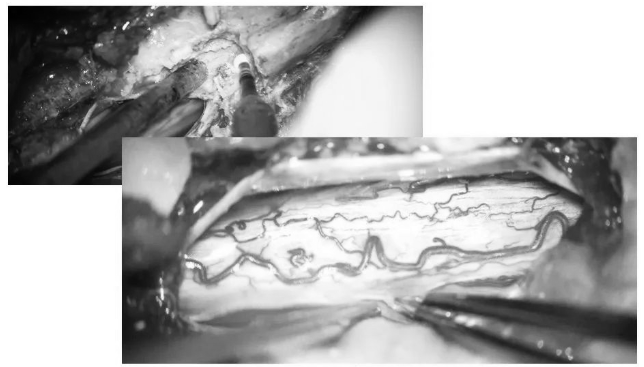

▼取下部分T5、T6椎板

▼术中超声定位海绵状血管瘤(白色)

▼术中超声显示髓内海绵状血管瘤超出骨窗大小,向T7方向生长,继续磨除部分T7椎板,扩大暴露范围

▼沿后正中切开,即可见含铁血黄素沉积带及陈旧性血凝块